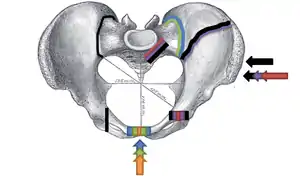

Superior view, Pelvic Fracture Types (2006).

Force and break are shown by matching color:

Anteroposterior compression type I (orange), Anteroposterior compression type  II (green), Anteroposterior compression type III (blue); Lateral compression type I (red), Lateral compression type II (purple), F. Lateral compression type III (black).

Increased force and breaks are shown by increasing size.

Superior view, Pelvic Fracture Types (2006). Force and break are shown by matching color: Anteroposterior compression type I (orange), Anteroposterior compression type II (green), Anteroposterior compression type III (blue); Lateral compression type I (red), Lateral compression type II (purple), F. Lateral compression type III (black). Increased force and breaks are shown by increasing size.

This fracture is best viewed anteriorly, while the other fractures are viewed superiorly. The arrow indicates where the force is coming from, and the colored lines indicate where the break occurs.

The Young-Burgess classification system is based on mechanism of injury: anteroposterior compression type I, II and III, lateral compression types I, II and III, and vertical shear,[5] or a combination of forces.